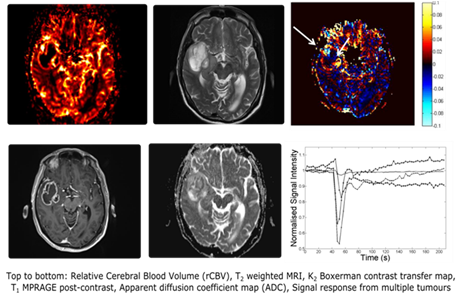

• developing the use of dynamic susceptibility contrast MRI in neuro oncology, for example, to investigate pseudo progression in glioblastomas

MRI-2